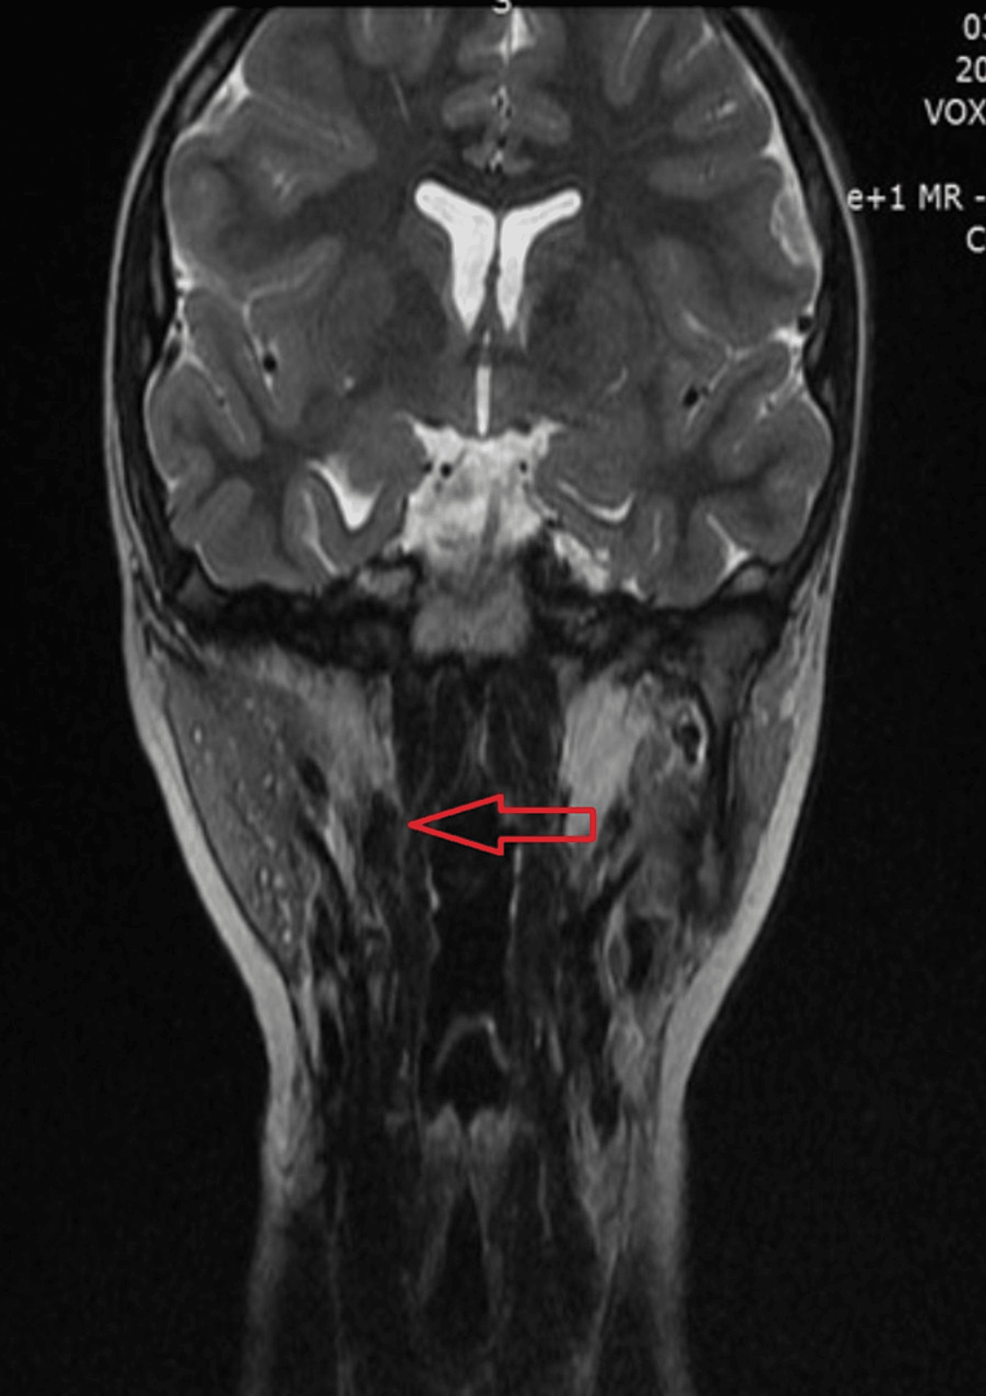

From www.cureus.com

Retropharyngeal Ectopic Thymus in a Pediatric Patient With 22q11.2 Thymus In Infants Infants with congenital heart disease requiring sternotomy often undergo thymectomy to clear the surgical field. Thymic hyperplasia refers to the enlargement or overgrowth of the thymus gland. Many patients remain asymptomatic despite It can be caused by various factors, including. To assess the variation in size of the thymus in vivo in preterm neonates and to identify relations between thymic. Thymus In Infants.